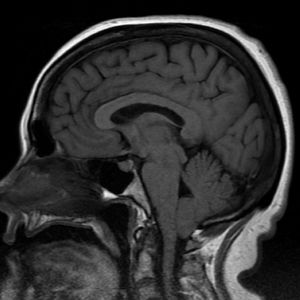

Patient (17 year old) had been complaining of occipital headaches, loss of balance, memory loss, tingling in hands and arms and fainting. They did an MRI. What's the problem?

Wallenberg sendrome

Herniation?